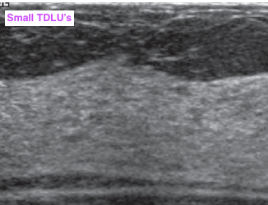

• TDLUs

• ~2mm hypoechoic structures

• Larger with adenosis + pregnancy